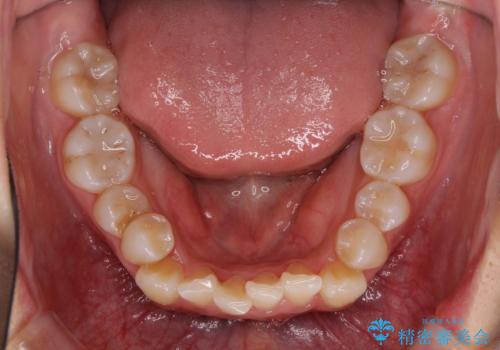

- 前歯のでこぼこと乳歯が残るほどの八重歯を気にして来院された患者様です。

非抜歯にてワイヤー矯正にて治療することとしました。(ただし、親知らずと乳歯は抜歯)

犬歯は歯根が太く長いため、移動には時間を要します。しかし、犬歯は機能面から考えて残すことを選択したいため、長期間をかけて治療を行うこととしました。